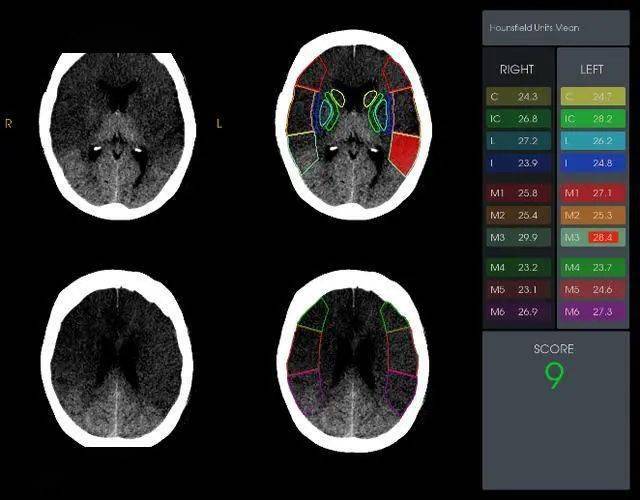

rapidai缺血aspects评分rapidai脑血管cta分析出大血管闭塞rapidai ct

术前头颅ct:右侧额顶颞叶脑实质片状密度减低,aspect 2分.

ct 评分(alberta stroke program early ct score,aspects)是评价缺血